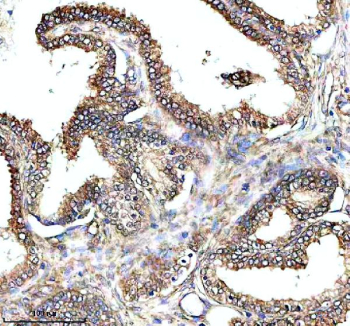

IHC analysis of PAM using anti-PAM antibody. PAM was detected in a paraffin-embedded section of human prostate cancer tissue. Heat mediated antigen retrieval was performed in EDTA buffer (pH 8.0, epitope retrieval solution). The tissue section was blocked with 10% goat serum. The tissue section was then incubated with 2 ug/ml rabbit anti-PAM antibody overnight at 4oC. Peroxidase Conjugated Goat Anti-rabbit IgG was used as secondary antibody and incubated for 30 minutes at 37oC. The tissue section was developed using an HRP secondary and DAB substrate.